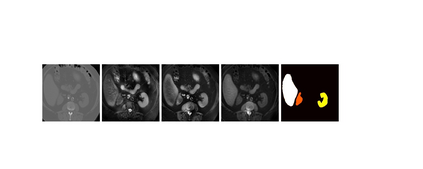

This work presents a novel framework CISFA (Contrastive Image synthesis and Self-supervised Feature Adaptation)that builds on image domain translation and unsupervised feature adaptation for cross-modality biomedical image segmentation. Different from existing works, we use a one-sided generative model and add a weighted patch-wise contrastive loss between sampled patches of the input image and the corresponding synthetic image, which serves as shape constraints. Moreover, we notice that the generated images and input images share similar structural information but are in different modalities. As such, we enforce contrastive losses on the generated images and the input images to train the encoder of a segmentation model to minimize the discrepancy between paired images in the learned embedding space. Compared with existing works that rely on adversarial learning for feature adaptation, such a method enables the encoder to learn domain-independent features in a more explicit way. We extensively evaluate our methods on segmentation tasks containing CT and MRI images for abdominal cavities and whole hearts. Experimental results show that the proposed framework not only outputs synthetic images with less distortion of organ shapes, but also outperforms state-of-the-art domain adaptation methods by a large margin.